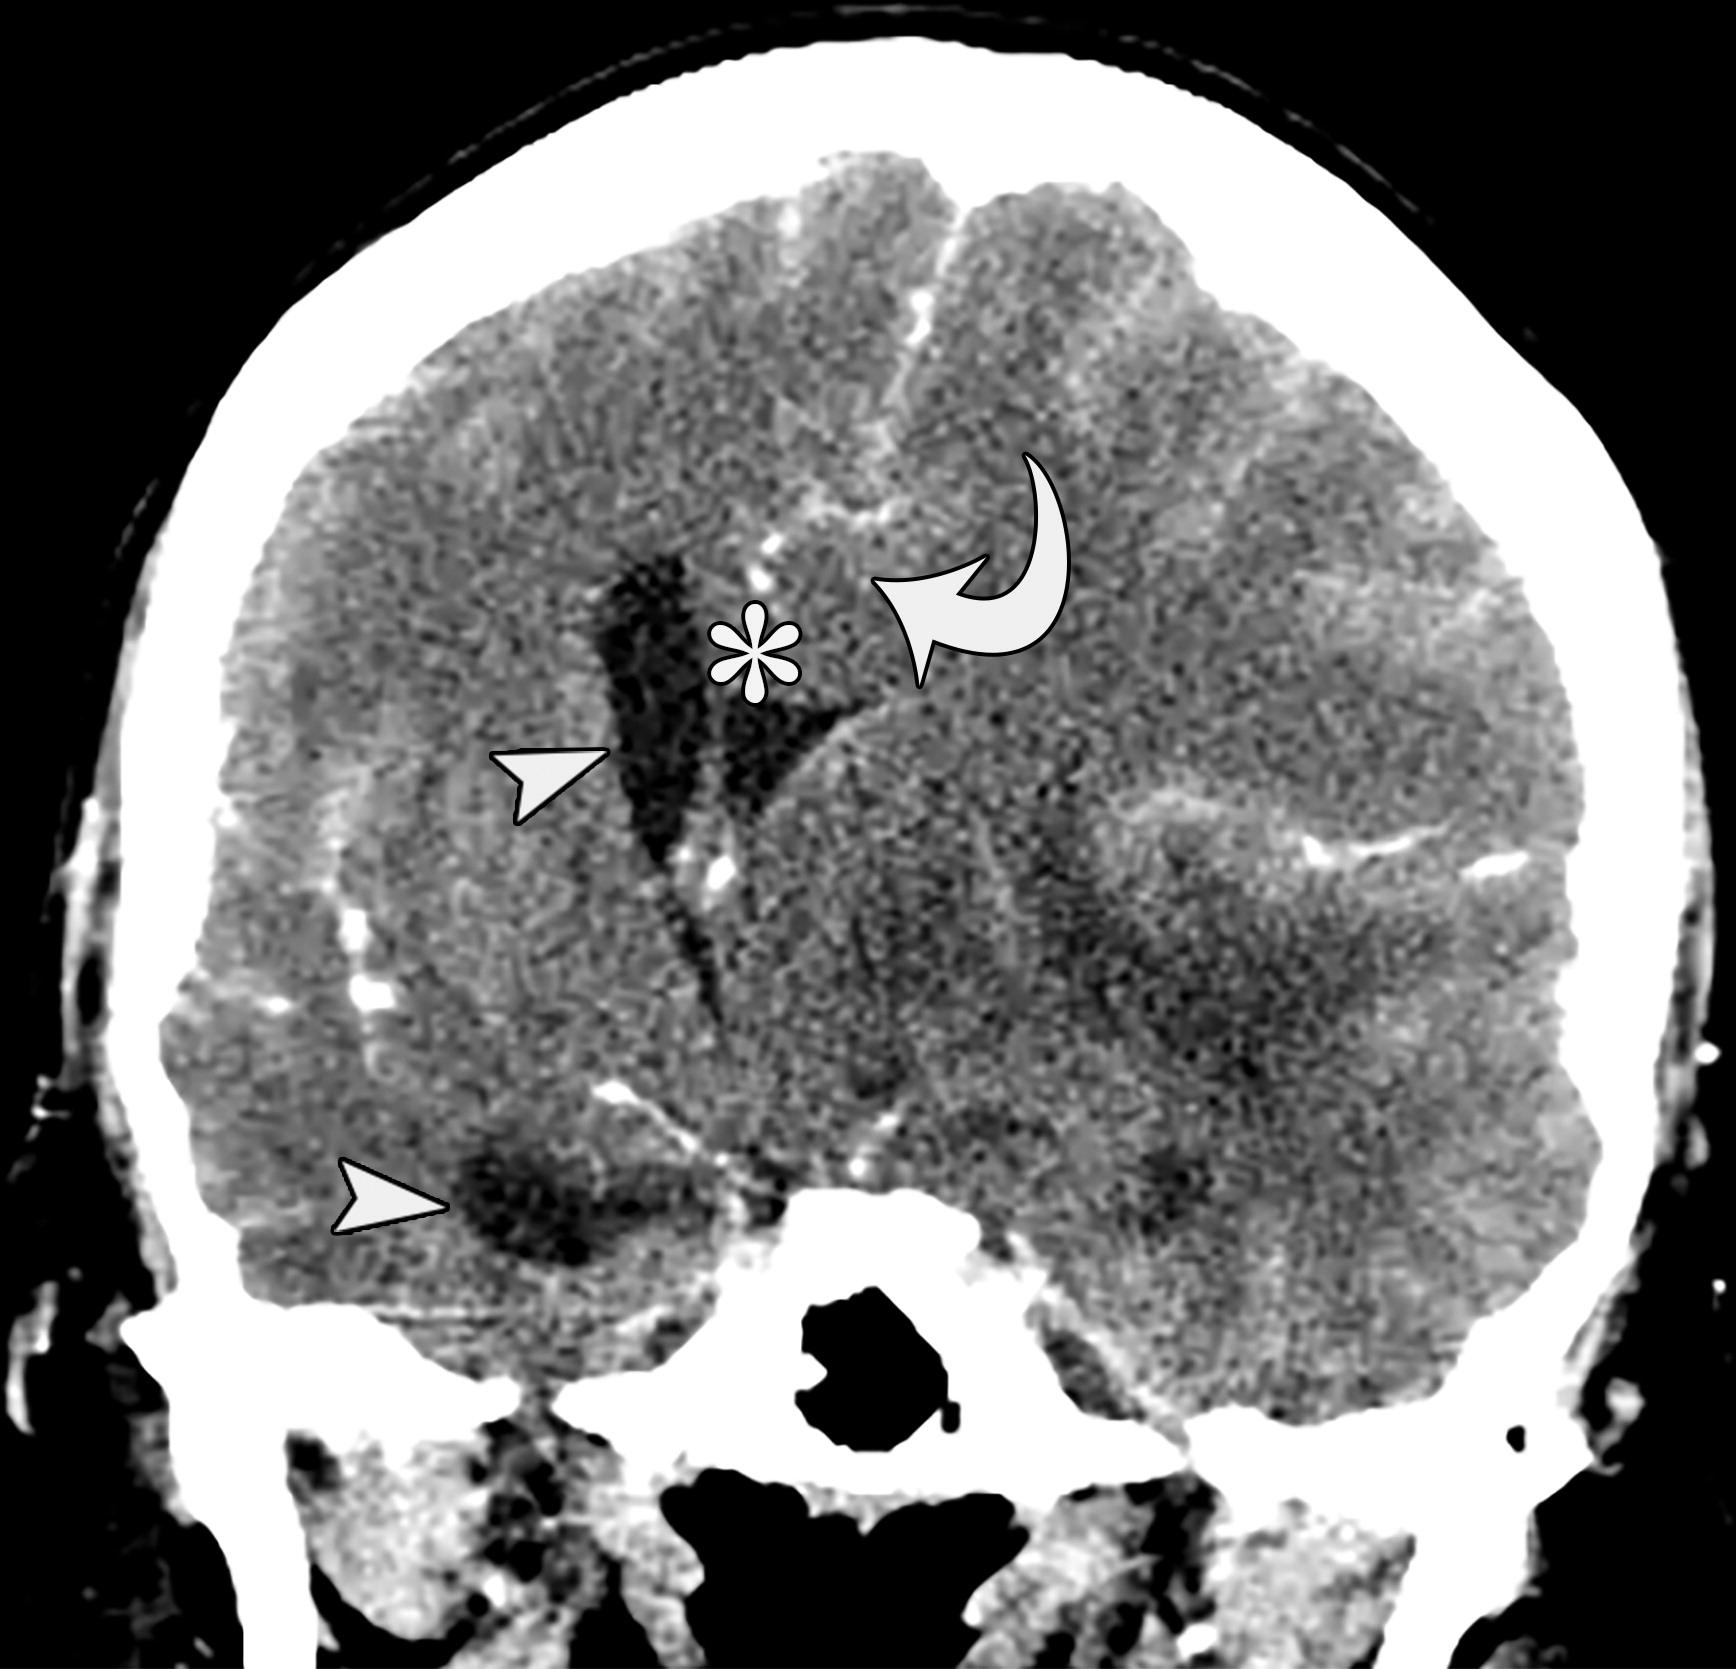

e10b81f69aecfde7ed5f5612478dbcdc.jpeg

33岁男性,生殖细胞肿瘤脑转移患者的大脑镰下疝:冠状增强CT示大脑穹隆游离缘下方的扣带回从左向右疝入(白色弯箭头),并伴同侧胼胝体(*)的下侧移位,注意同侧脑室受压和对侧脑室的扩张(白色箭头)。